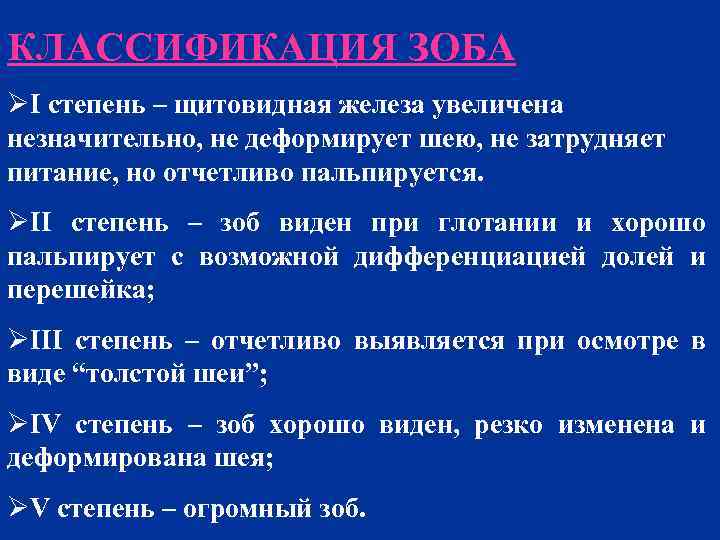

КЛАССИФИКАЦИЯ ЗОБА ØI степень – щитовидная железа увеличена незначительно, не деформирует шею, не затрудняет питание, но отчетливо пальпируется. ØII степень – зоб виден при глотании и хорошо пальпирует с возможной дифференциацией долей и перешейка; ØIII степень – отчетливо выявляется при осмотре в виде “толстой шеи”; ØIV степень – зоб хорошо виден, резко изменена и деформирована шея; ØV степень – огромный зоб.

КЛАССИФИКАЦИЯ ЗОБА ØI степень – щитовидная железа увеличена незначительно, не деформирует шею, не затрудняет питание, но отчетливо пальпируется. ØII степень – зоб виден при глотании и хорошо пальпирует с возможной дифференциацией долей и перешейка; ØIII степень – отчетливо выявляется при осмотре в виде “толстой шеи”; ØIV степень – зоб хорошо виден, резко изменена и деформирована шея; ØV степень – огромный зоб.